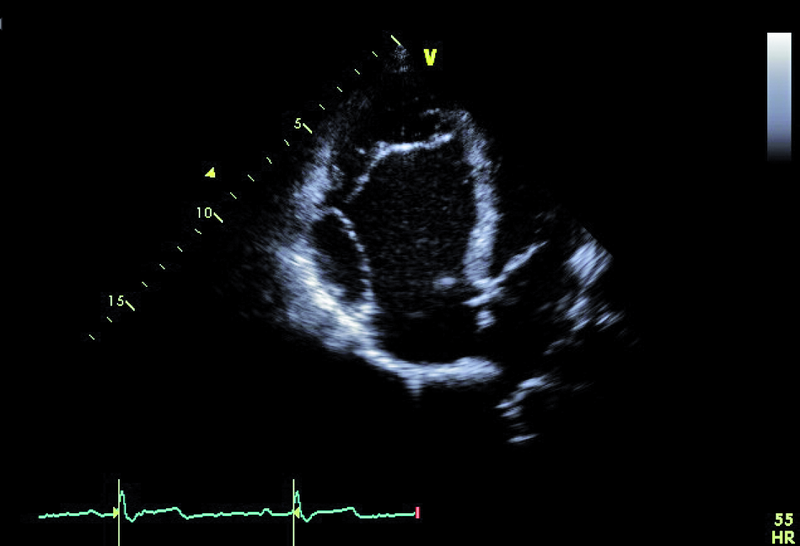

Chłopiec, lat 16, z niedoborem masy ciała (waga 55 kg, wzrost 176 cm), deformacją klatki piersiowej, palący tytoń, został przyjęty do kliniki po dwóch incydentach omdleń podczas pobierania krwi. Pacjent wcześniej był pod opieką ośrodka kardiologii dziecięcej z powodu zmian morfologicznych zastawki trójdzielnej typowych dla anomalii Ebsteina. Wobec niewielkiego nasilenia patologii kardiolodzy dziecięcy nie proponowali rodzicom leczenia operacyjnego i zalecili okresową kontrolę. W badaniu przedmiotowym stwierdzono prawidłowe zabarwienie powłok i uwypuklenie lewej połowy klatki piersiowej. Podczas osłuchiwania zwracała uwagę wielotonowość, częstość serca była miarowa i wynosiła ok. 60 uderzeń na minutę, słyszalny był szmer skurczowy o głośności 3/6 w dolnej części mostka. Wykluczono hepatosplenomegalię. W EKG rejestrowano rytm zatokowy miarowy. W teście wysiłkowym chłopiec osiągnął 75% limitu tętna (obciążenie 150 W=8,6 MET). Po zakończeniu wysiłku saturacja wynosiła 98%, pojawiła się ekstrasystolia nadkomorowa o łagodnym nasileniu. W żadnym z badań nie obserwowano istotnej bradyarytmii. W zdjęciu przeglądowym klatki piersiowej serce było powiększone, a rysunek naczyniowy skąpy.

Cechy anomalii Ebsteina łatwo zidentyfikować. Należy zwrócić uwagę na odległość między przyczepem płatka przegrodowego zastawki trójdzielnej a przyczepem przedniego płatka zastawki mitralnej (ryc. 1). Fizjologiczne przesunięcie płatków jest niewielkie i zwykle nie przekracza 5-10 mm. Za kryterium rozpoznania anomalii uważa się wartość 20 mm (w przedstawionym przypadku 50 mm). Przemieszczone płatki są zwykle zmienione organicznie, pogrubiałe, często pociągane przez struny ścięgniste. Płatek przedni jest prawidłowo przyczepiony do pierścienia zastawki trójdzielnej, natomiast jest zwykle powiększony i kształtem może przypominać żagiel (ryc. 1-3). Cechą płatka przedniego w anomalii Ebsteina jest także jego nadmierna ruchomość i liczne perforacje powodujące zwykle więcej niż jedną falę zwrotną (ryc. 4). Zatrializowana część prawej komory znajduje się między przemieszczonymi przyczepami płatków przegrodowego i tylnego, a właściwa jama ma zmniejszoną pojemność. To, czy wada daje objawy, zależy od nasilenia niedomykalności trójdzielnej i od współistniejących anomalii. Niedomykalność trójdzielna u tego pacjenta, mimo dużego przemieszczenia płatka przegrodowego, była mała (ryc. 4). Zarejestrowany metodą doplerowską profil prędkości z jednego ze strumieni niedomykalności wskazywał na niepodwyższone ciśnienie w jamie prawej komory (ryc. 5). Funkcja mięśnia prawej komory określona za pomocą pomiaru przemieszczenia bocznej części pierścienia zastawki trójdzielnej była prawidłowa (ryc. 6). Diagnostykę można na tym etapie zakończyć i uznać, że chory kwalifikuje się do dalszej obserwacji. Badanie przezprzełykowe jest potrzebne u pacjentów, u których nie można ocenić dokładnie morfologii zastawki trójdzielnej. Może też być konieczne w przypadku desaturacji krwi tętniczej i podejrzenia często towarzyszącego anomalii ubytku przegrody międzyprzedsionkowej. Warto zaznaczyć, że ubytek zwykle charakteryzuje się przeciekiem prawo-lewym, na skutek dysfunkcji jam prawego serca i wzrostu ciśnienia w jamie prawego przedsionka. W tym przypadku, wobec braku sinicy, badania przezprzełykowego nie wykonano. Cewnikowanie serca także nie jest konieczne, ponieważ chory ma małą niedomykalność trójdzielną i dobrą wydolność fizyczną, a więc nie kwalifikuje się do leczenia operacyjnego.